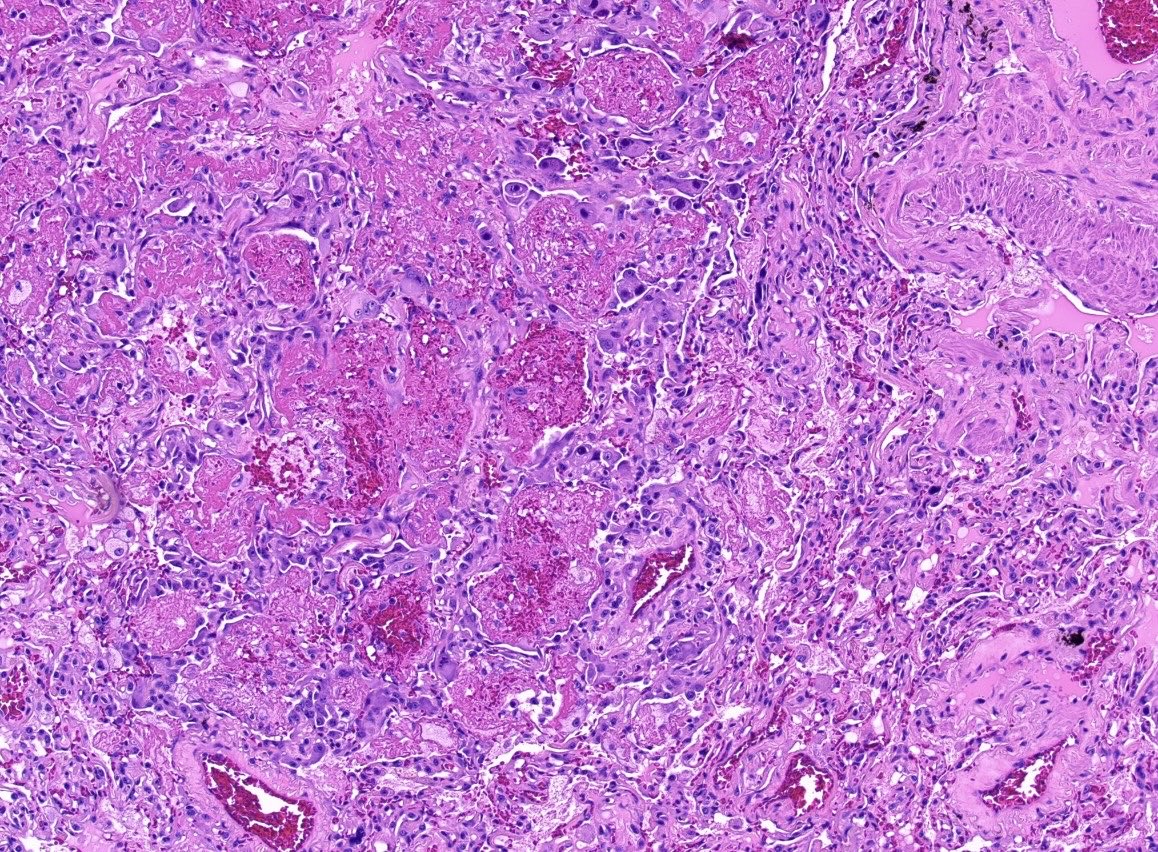

Radical orchidectomy Intratubular embryonal carcinoma with necrosis (in images) There was adjacent mixed germ cell tumour including embryonal carcinoma #PathTwitter #Pathology #PathResidents #GUPath

DrLaurenceGalea's tweet image. Radical orchidectomy

Intratubular embryonal carcinoma with necrosis (in images)

There was adjacent mixed germ cell tumour including embryonal carcinoma

#PathTwitter #Pathology #PathResidents #GUPath